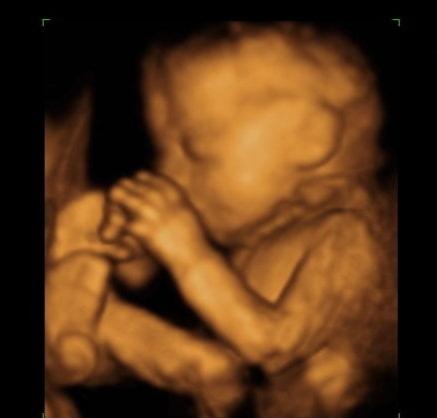

这种情况也很常见,我们可以从网上看到很多胎儿捂着脸的四维照片,很多孕妈妈诉苦说“宝宝总是捂着脸,一会儿捂鼻子、一会儿捂脑袋、一会儿捂嘴巴,做个四维真的很费劲。”

做四维彩超的时间是怀孕20-28周,在这期间,胎儿发育迅速,身长约30厘米,体重约600g,像个哈密瓜那么大。胎儿已经占据了子宫绝大部分空间,子宫内空间变得拥挤。胎儿为了适应狭窄的生存环境,只好抱住头、蜷缩着身子。

胎儿手的位置基本处于向上的状态,不是摸头,就是揉眼睛、捏鼻子、吸吮手指。这些都是他日常的一些活动,没有什么特别的。当胎儿出生以后,宝宝的手总是向上举着,呈现投降的姿势,就是因为在子宫里形成的习惯。

做四维彩超的时候,探头会有热效应,胎儿会感觉到这种热,有些不舒服。同时探头在肚皮上滑动时,对胎儿有触碰。这时的胎儿触觉敏感,他会下意识地提高警惕,捂住脸是一种最自然的表达方式。

所以,做四维彩超时胎儿捂住脸,虽然给孕妈妈制造了不少麻烦,但实际上都是他的正常行为,同时说明他手的灵活性是没问题的,孕妈妈们不要太担心了。